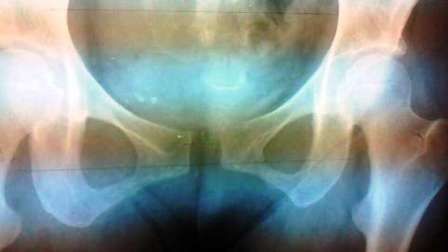

上の図の「恥骨結合」の部分、左右の茶色の中心部分

(骨盤の下の方)が広がった状態が

「骨盤が広がった」状態です。

レントゲン写真で見るとこんな感じです↓

広がっているだけでなく、骨盤の歪み(ゆがみ)がひどい場合の

レントゲン写真は、こんな感じです↓

真ん中の「恥骨結合」の部分が上下にズレているのがわかると思います。

ここまで、ズレている方は少ないものの、

骨盤の下側が広がっている方は、現代は非常に多くなってきています。